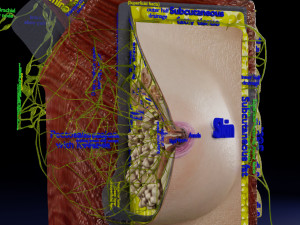

This is a 1:1 scaled model of right breast cut opened in sagittal plane to reveal its internal antomy and histology (schematic). The deeper parts and fascial layers are also depicted to give a very detailed approach to the model. The full layers starting from skin, nipple areola, till intercodtal muscles and ribs are also depicted.